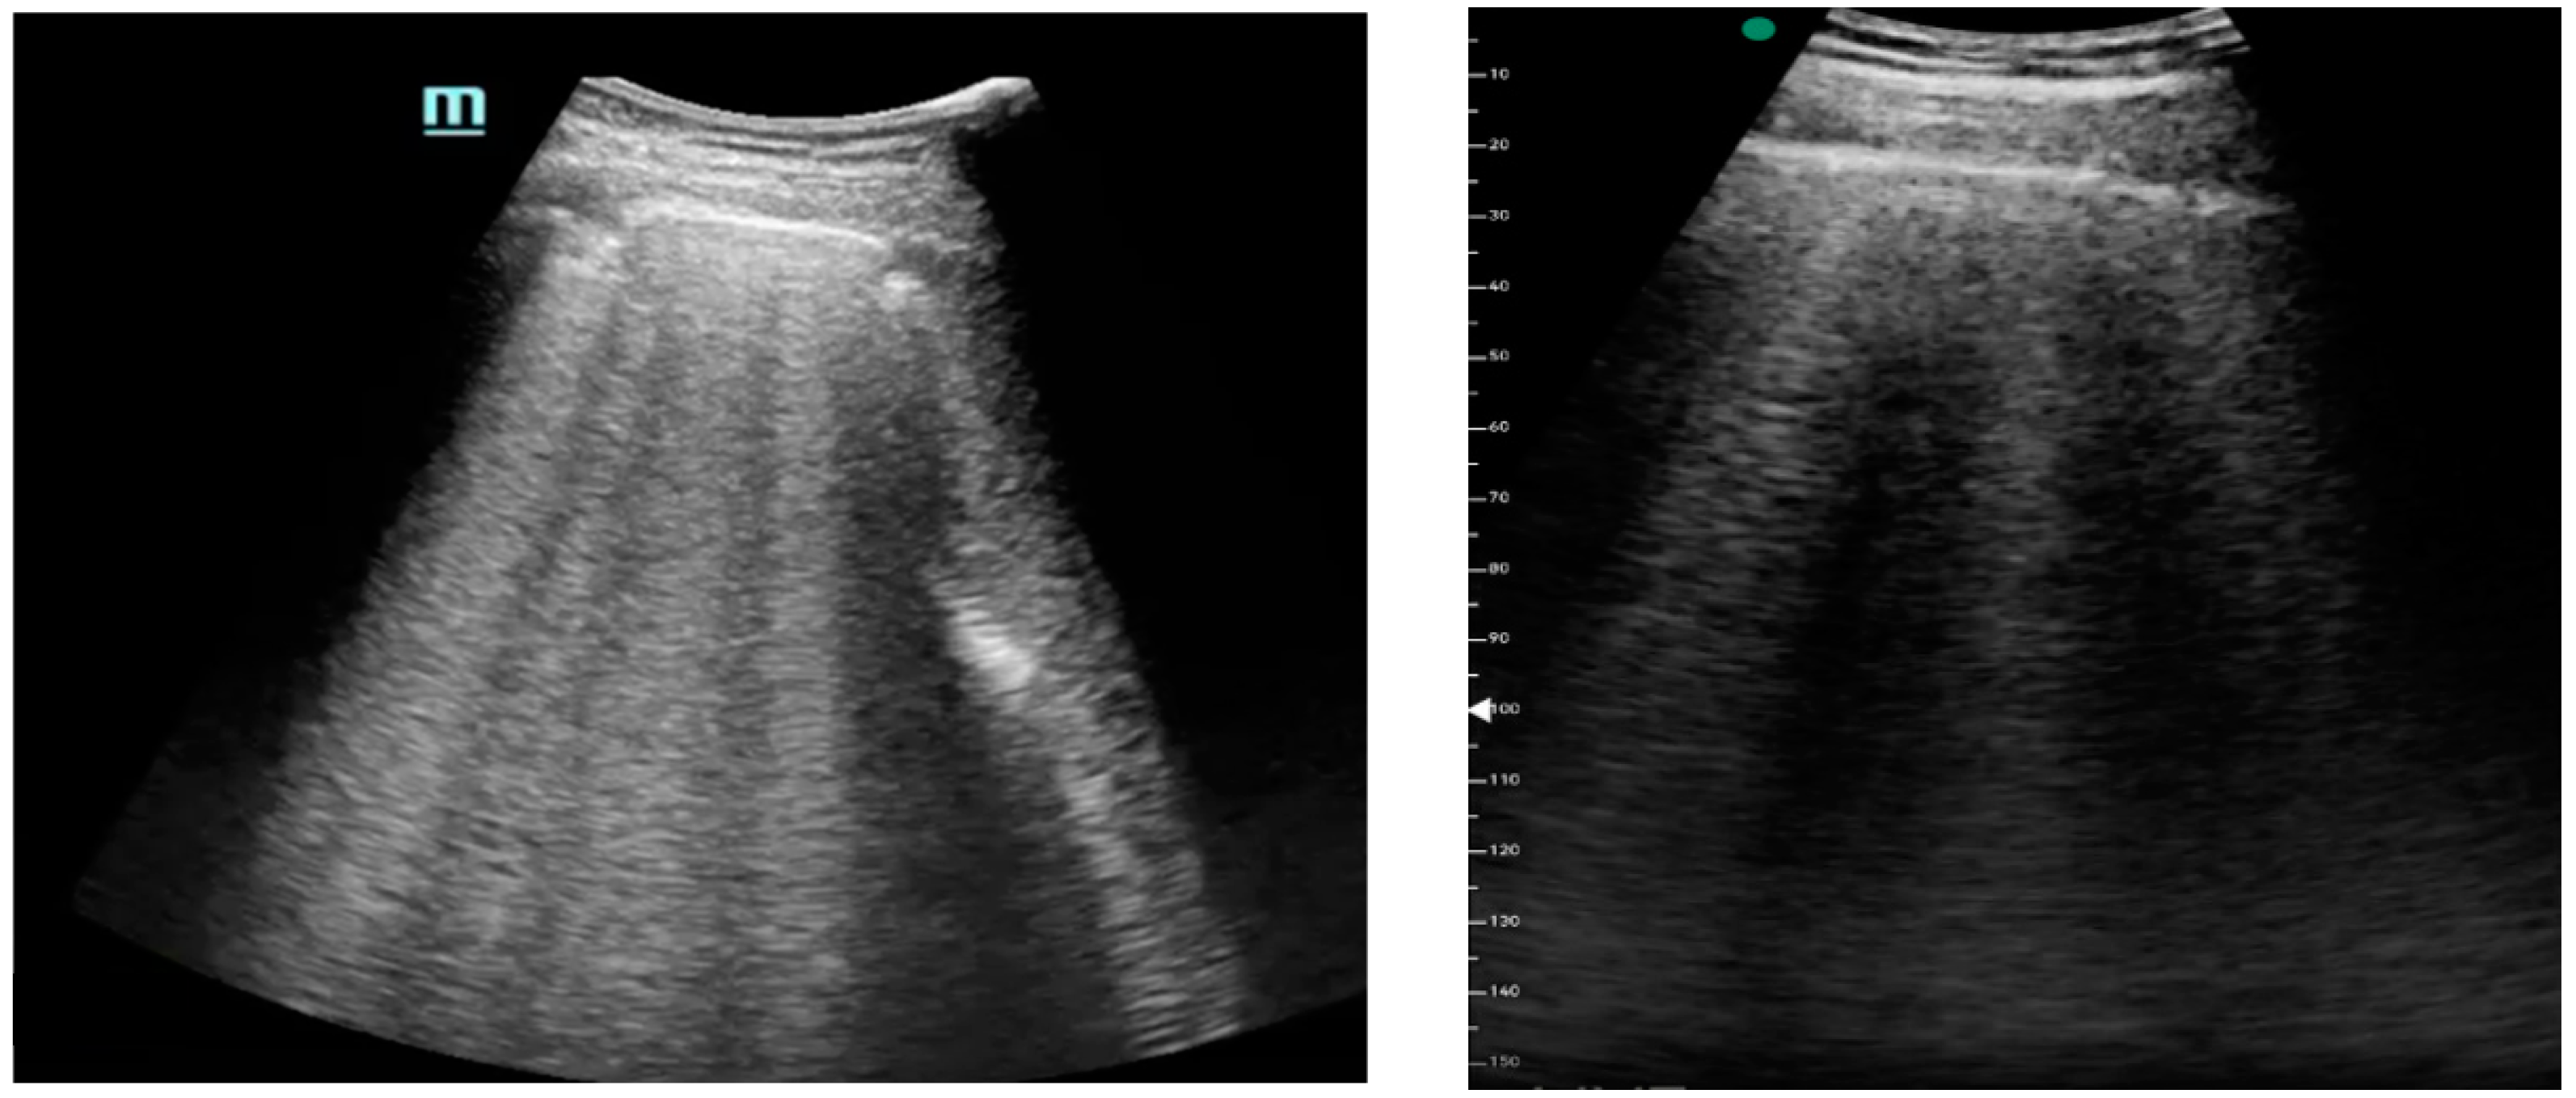

Figure 1, Figure 2 and Figure 3 exhibit characteristic examples of ultrasound still images from the videos captured via a standard ultrasound (left side) and portable handheld device (right side). Quality may slightly differ from that of the videos as these are still images.

Figure 1. B-lines.